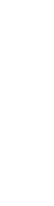

충치치료

충치치료

충치치료

치태 및 치석 속 세균이 치아를 부식시켜 손상된 경우 감염 속도가 빠른 충치만 제거한 후 수복 재료를 메워 기능을 회복시켜 줍니다.